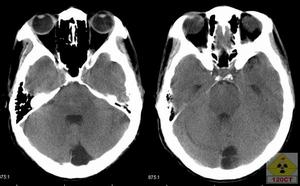

6.CT、MRI檢查

腦CT約半數顯示異常。炎性滲出物充填基底池及腦外側裂,部分患者腦實質內顯示結核瘤,直徑0.5~5cm,單發或多發,多位於額、顳及頂葉。增強掃描顯示環狀強化或密度增高。

腦MR採用Gd-DTPA增強,顯示基底池等部位強化,並較易發現腦實質內的結核瘤和小梗死灶。